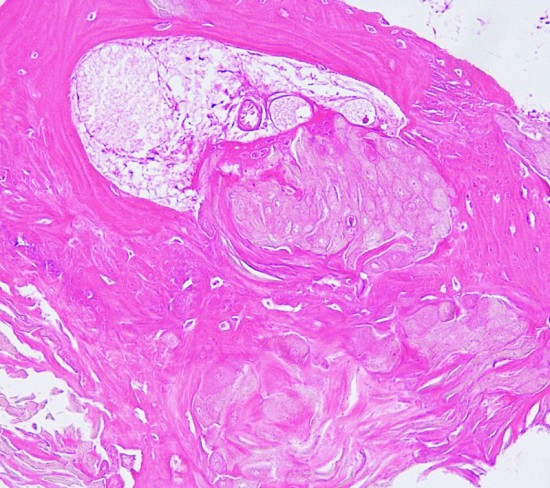

Scarce squamous epithelium with basal vascular network of cyst wall

Craniopharyngioma with wet keratin structures (upper left) and calcification (upper right).